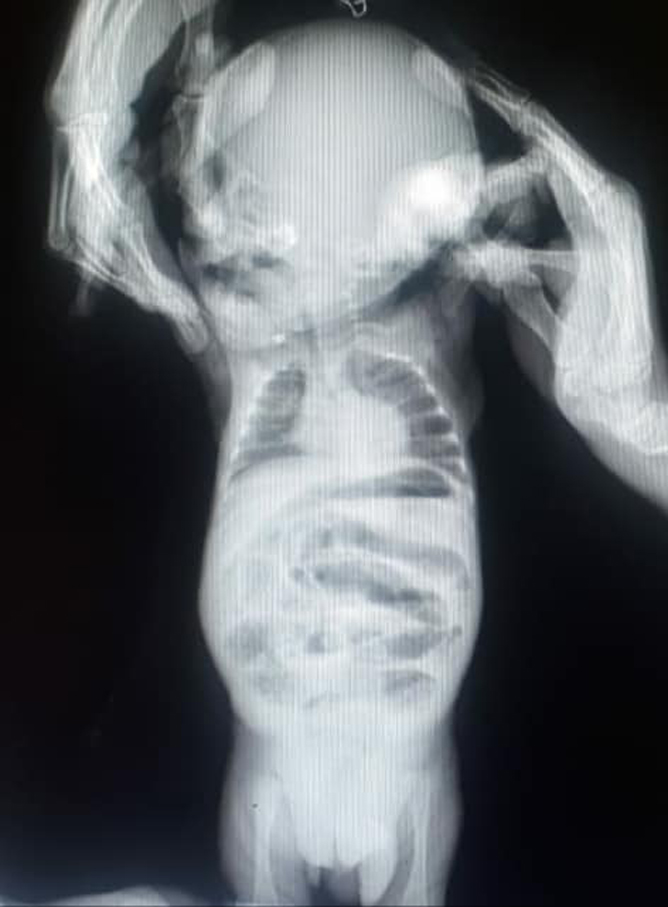

Və beləcə hadisənin üzərindən təqribən 48 saat keçdikdən sonra olduqca ağır vəziyyətdə bizim klinikaya çatdırıldı. Uşağı bu vəziyyətə salan boğulmuş qasıq yırtığı idi...

Ciddi qan azlığı, infeksiya dəyərlərində artış olsa da məcburi təcili əməliyyata aldıq. Təəssüf ki, keçən gecikdirilmiş 48 saat öz işini görmüşdü. Körpə sağ xayasını və bağırsağının bir qismini itirdi...

Bağırsaq yırtıq kisəsində boğulduğu üçün həm özünün, həm də xayanın qidalanması pozub nekroz eləmişdi, yəni çürümüşdü. Məcburi Sağ xaya çıxarıldı, nazik bağırsağın nekroz olunmuş hissəsi çıxarılaraq uc-uca tikildi. Əməliyyatdan sonra ağır vəziyyətdə neonotoloji reanimasiya şöbəsinə verildi. Neonotoloqlarımızın gərgin səyləri nəticəsində körpə ağır günləri geridə qoydu. Yenidən valideynlərinə qovuşdu və yaşadıqları rayona getdi.